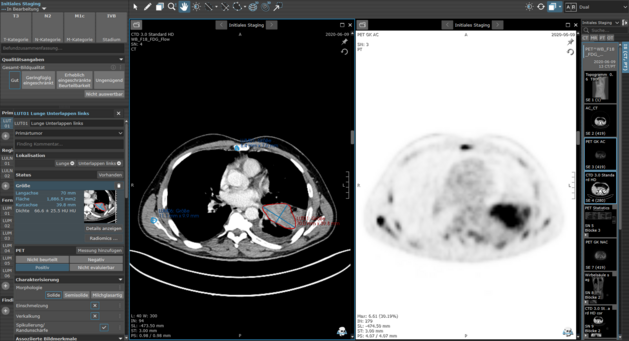

PET-Aufnahmen des Torsos mit relevanten falsch-positiven Befunden, markiert durch rote gestrichelte Kreise, und korrekt erkannten Läsionen (True Positives) in Grün

Repräsentative Vorhersagefehler in Fällen mit hohem Dice Similarity Coefficient (DSC)

LMU Klinikum München: Künstliche Intelligenz für das TNM-Staging beim NSCLC – Wie gut sind KI-basierte Segmentierungen wirklich?

Die aktuelle Studie „Artificial intelligence for TNM staging in NSCLC – a critical appraisal of segmentation utility in [18F]FDG PET/CT“ untersucht…